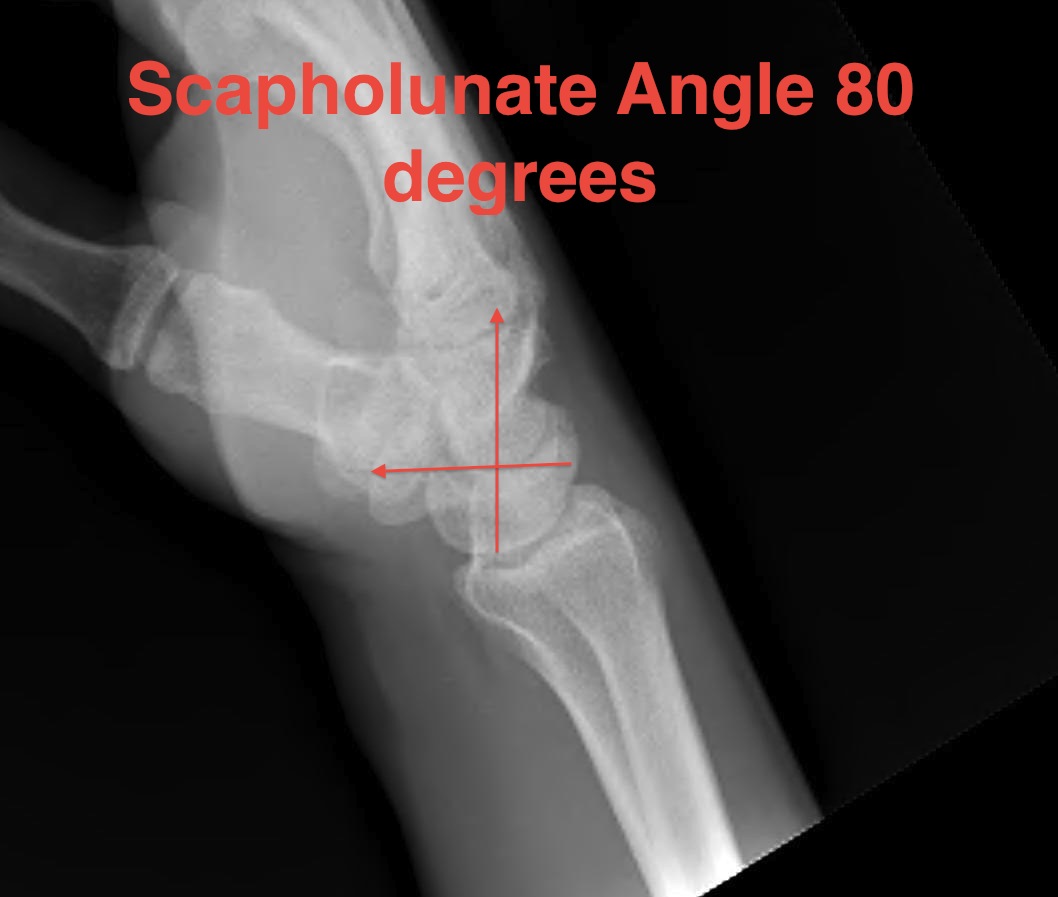

Lateral

Palmarflexion of scaphoid

Dorsiflexion of lunate

Increased scapholunate angle

- > 70o

- usually 30 - 60o

Increased luno-capitate angle

- normally < 10o

Increased radio-lunate angle

- lunate extended > 10o